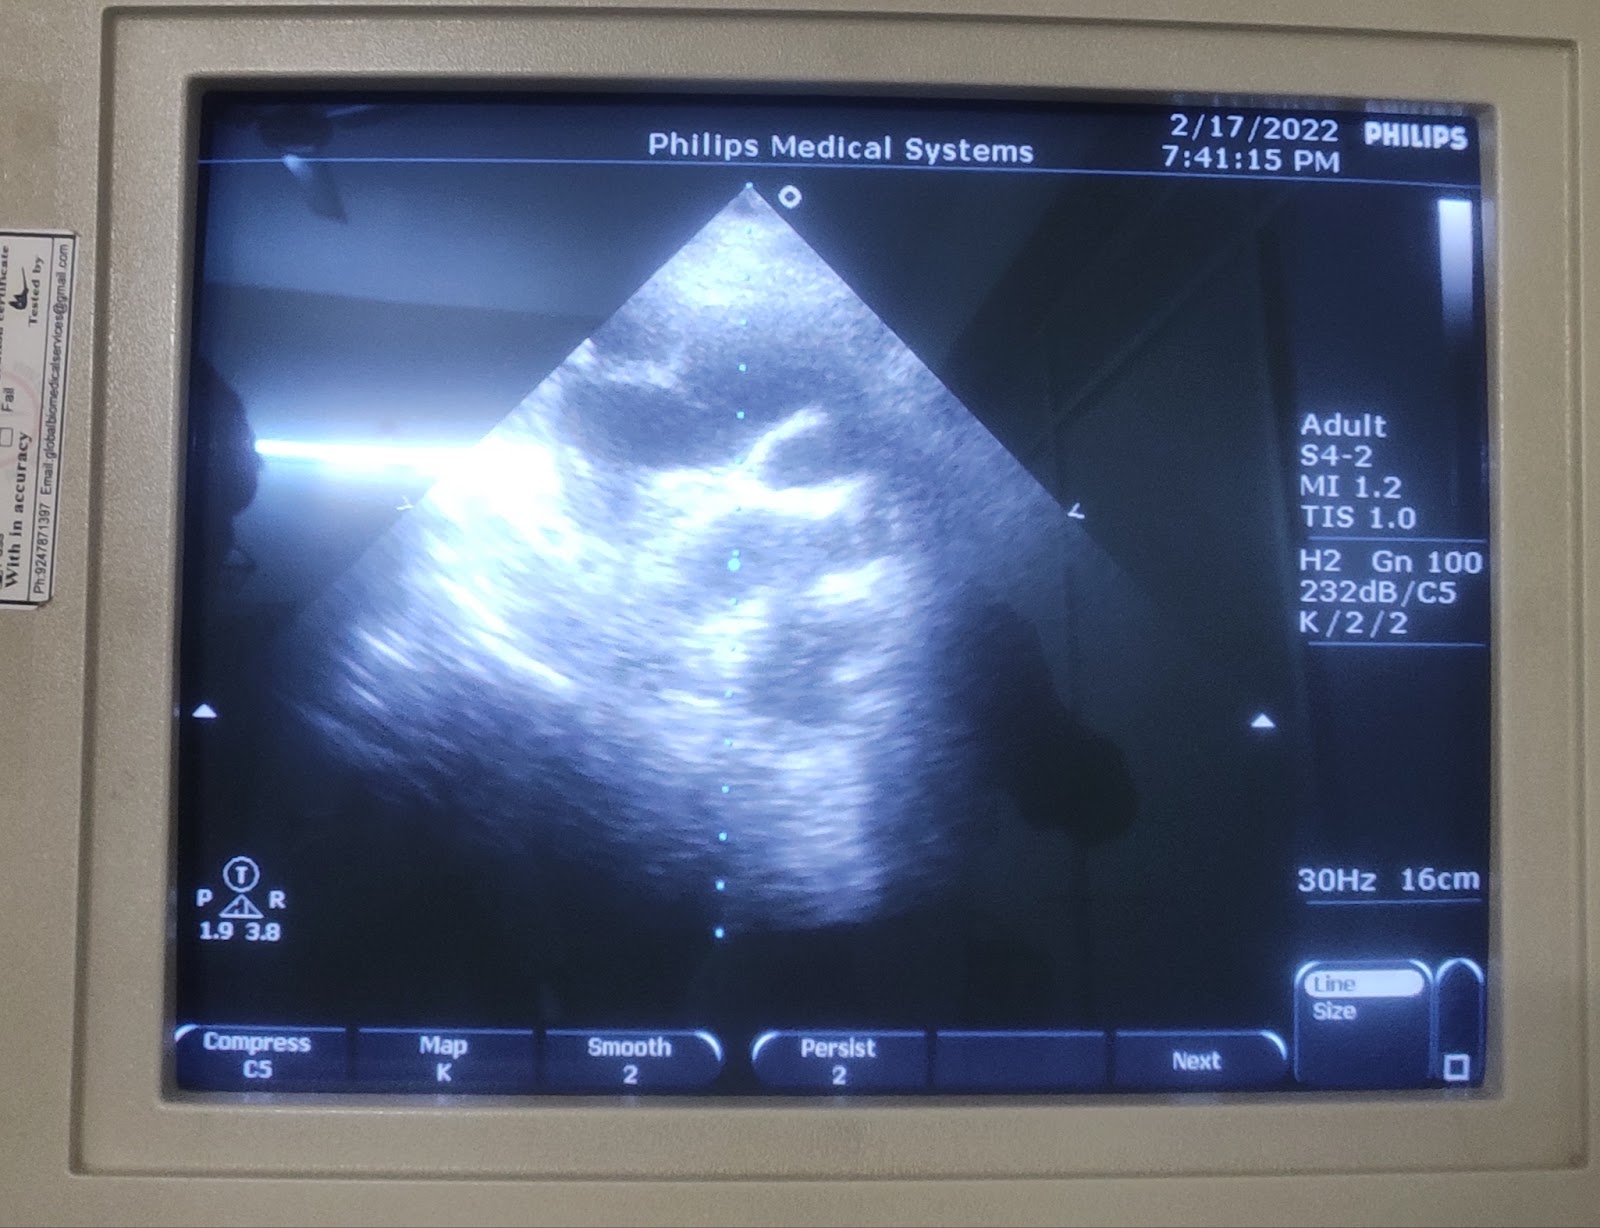

2D ECHO -